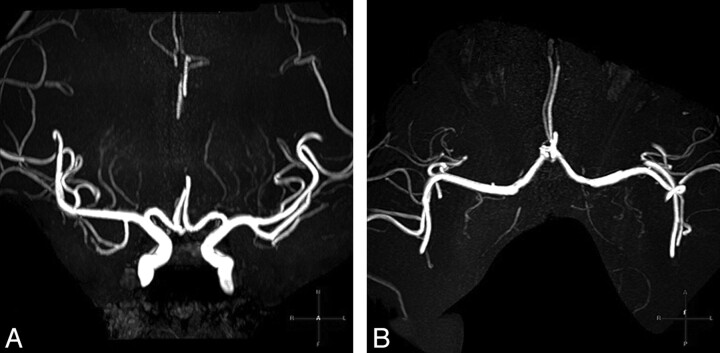

Fig 3.

3T 3D-TOF-MRA images of the LSAs of an age-matched nonhypertensive volunteer (a 32-year-old woman, BP = 126/78 mm Hg). Coronal MIP with a slab thickness of 20 mm (A) and an axial 20-mm MIP (B) clearly show the LSAs branching from the MCA and the ACA. The total number of the LSA stems counted from both sides is 7.